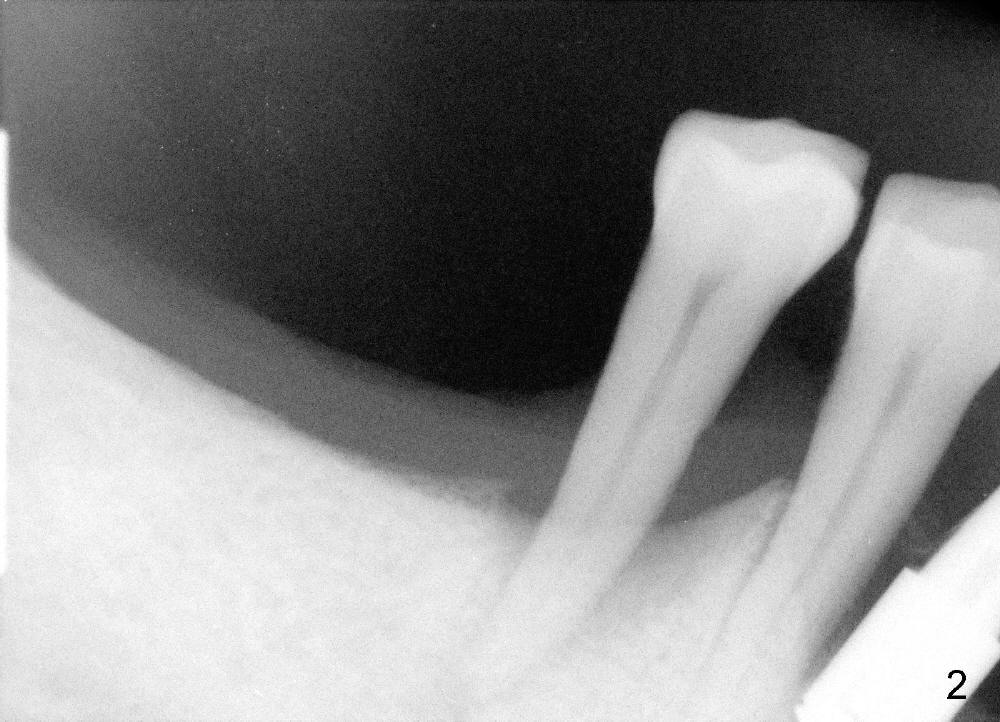

To avoid paresthesia on the right side, several preop PAs are taken (Fig.1-4) so that we know how to take good X-ray for this gagging patient. At first, #2 Sensor is used to take the first PA (Fig.1). It does not show the apex of the tooth #29. The second PA is a little better (Fig.2), but the mental nerve is out of view. Then #1 sensor is used. It allows us to position the sensor lower (Fig.3), but the image is blurred. When it is retaken, the image is clear (Fig.4), showing the proximity of the mental nerve loop (Fig.4': red dashed line) to the root tip of the tooth #29 (R).